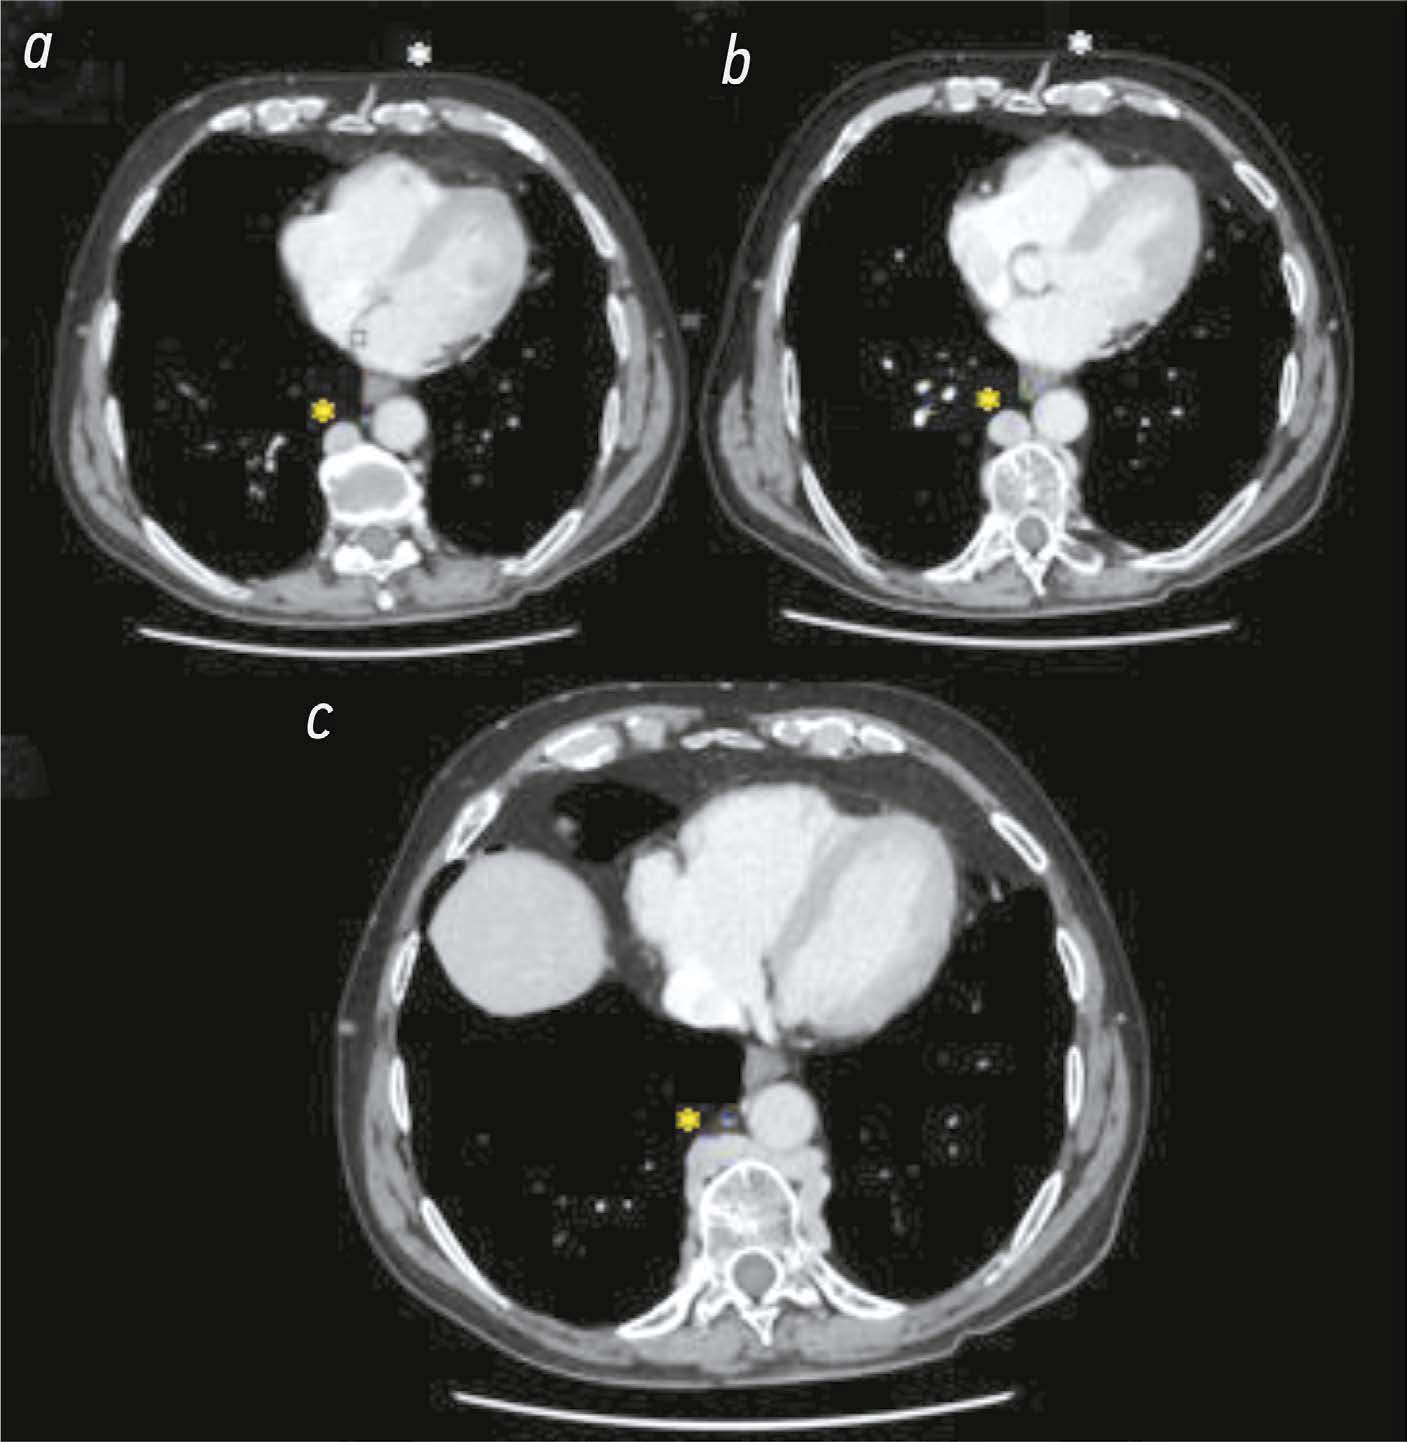

Hypoplasia of the inferior vena cava with hypertrophic azygos/hemiazygos and collateral venous circles of the abdomen: a case report

Hypoplasia of the inferior vena cava is a rare congenital vascular defect with various forms; thus, identifying a specific anatomical variant in the literature is challenging. In some cases, the inferior vena cava may also be interrupted. Herein, we present a unique case of of an unknown subrenal hypoplasia of the inferior vena cava with azygos and hemiazygos hypertrophy and the creation of several collateral circles, particularly in the anterior wall of the abdomen, in an asymptomatic 75 year old man. This report not only describes this unusual instance but also quickly demonstrates the variations of the venous system in the abdomen, particularly on the right side, and the inferior vena cava and the azygos system, and explains the significance of imaging in recognizing vascular anomalies. The case was explored using a multiphase computed tomography technique, which correctly identified this complex vascular anomaly. The patient had never experienced symptoms associated with the same vascular defect previously. Moreover, his symptoms did not appear to be related; therefore, a periodic follow up was recommended.